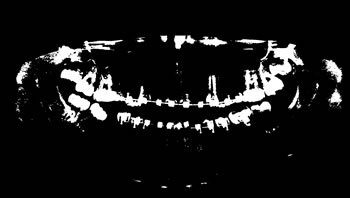

Image annotation

The process of annotating the images of our proposed data set occurred in two parts. First, it was initiated by the upper jaw through the annotation of the third right upper molar and making the annotation of all the teeth of the upper arch to the third left upper molar. Then, the same process was performed on the lower jaw with all the teeth, and in the same direction as the upper jaw, from left to right, starting with the annotation of the third right lower molar, and annotating all teeth from the lower arch to the lower third molar. Figure 4 illustrates the tooth annotation process through a panoramic X-ray image of the data set.